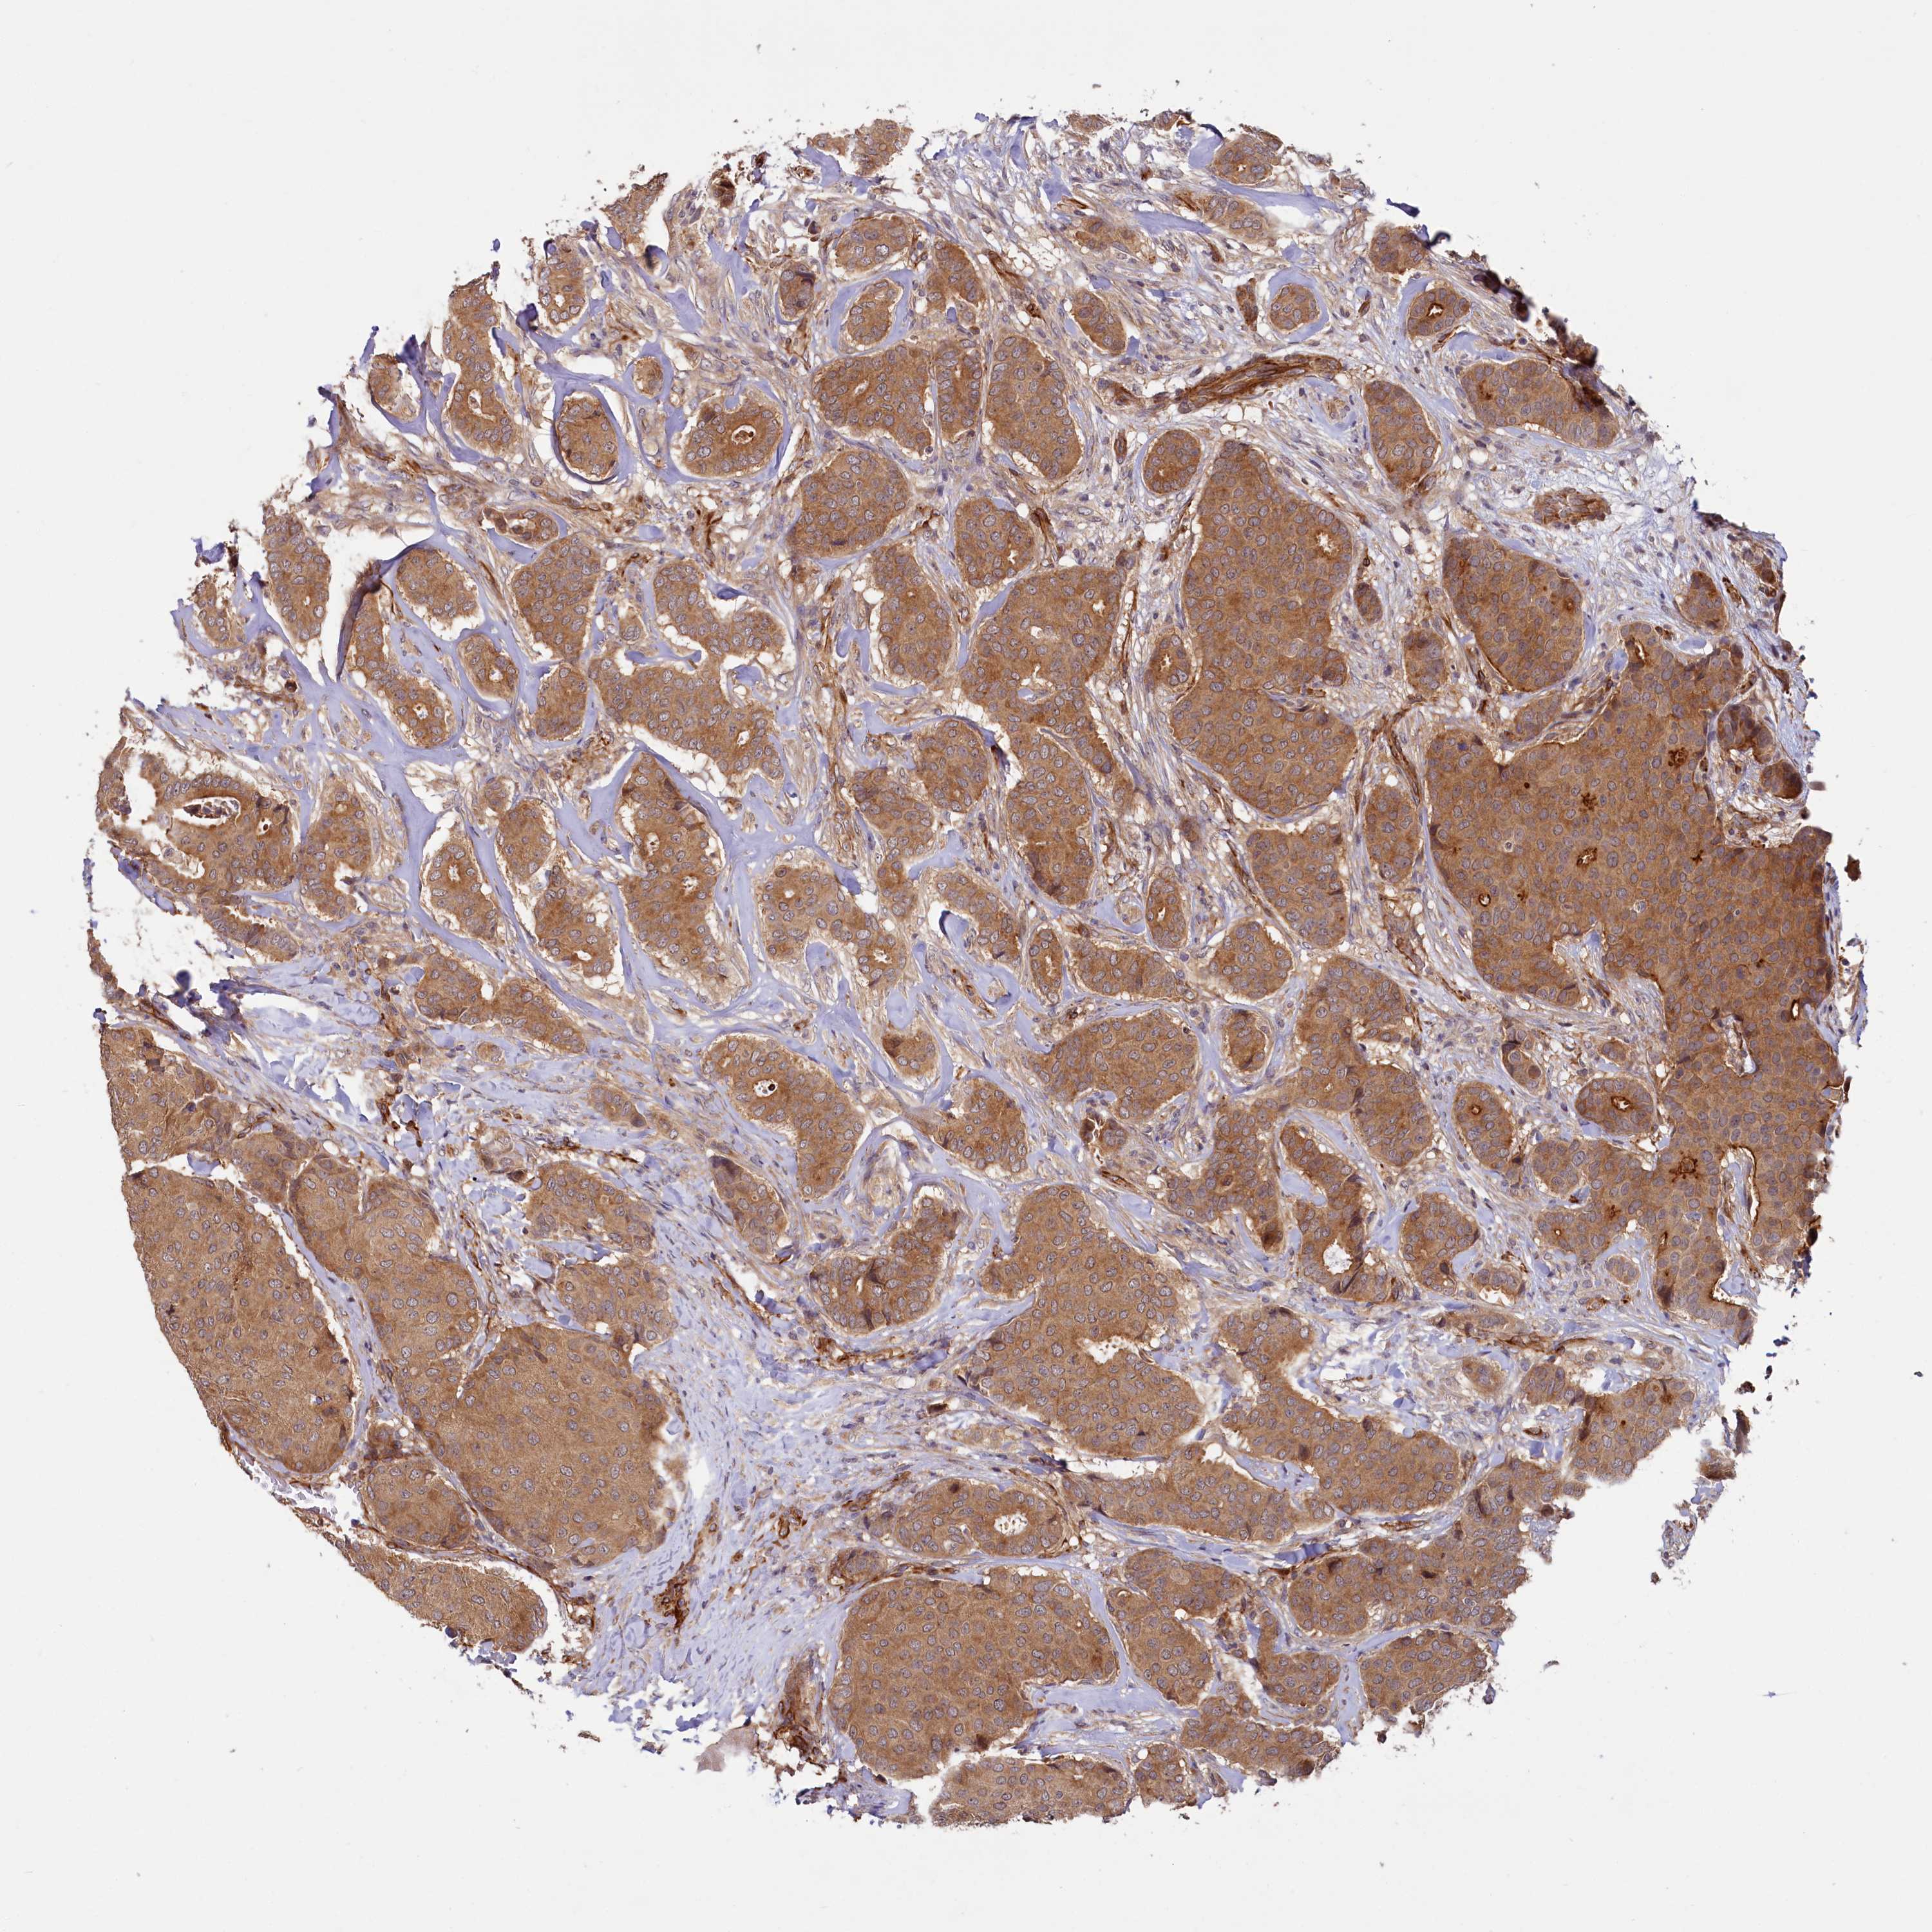

BRCA TCGA BRCA VALIDATION PROTEIN EXPRESSION

ANTIBODIES

AND

VALIDATION